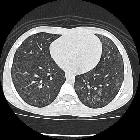

CT

The HRCT pattern can vary with time of onset of the hemorrhage and the clinical context is crucial in image interpretation:

- 2–3 days

- intralobular lines and smooth interlobular septal thickening superimpose on areas of ground-glass opacity

- may sometimes give rise to a crazy-paving pattern

- these can often resolve